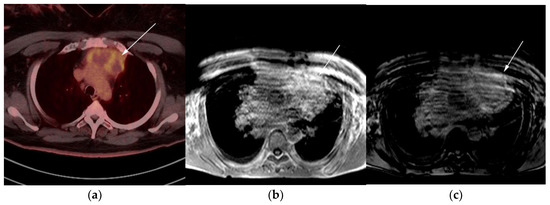

Figure 7.

Imaging in a 20-year-old female with history of classic Hodgkin’s lymphoma (CHL) who had 4 cycles of chemotherapy. (a) Axial 18F-FDG PET/CT showing residual wedge-shaped/triangular activity seen within the anterior mediastinum (arrow). There was concern for residual disease vs. thymic rebound hyperplasia. (b) MRI axial T1 in phase and (c) MRI axial T1 out of phase show intermedial signal on T1 in phase (arrow) with dropped signal on the out of phase sequence (arrow), consistent with fat content due to thymic rebound hyperplasia.

Figure 8.

Imaging in a 60-year-old female presenting with ill-defined anterior mediastinal mass. (a) Axial 18F-FDG PET/CT showing ill-defined hypermetabolic mass within the anterior mediastinum (arrow). This was biopsy-proven thymic carcinoma. (b) MRI T1 in phase sequence, (c) MRI T1 out of phase—note there is no dropped signal on the T1 out of phase (arrows) due to lack of fat. This is consistent with residual disease.